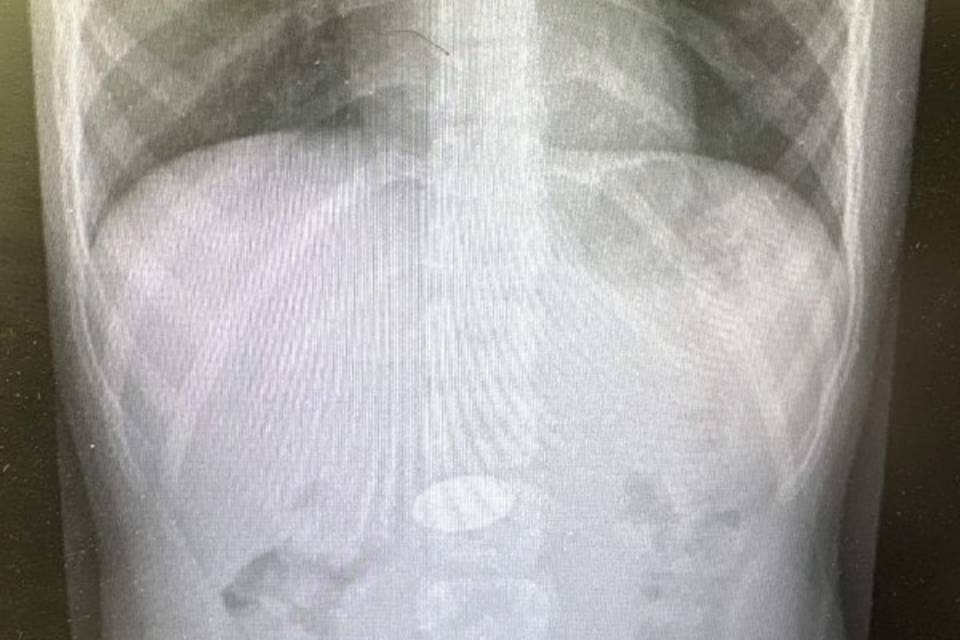

В детское хирургическое отделение клинической больницы №7 поступил маленький ребенок. Врачи обнаружили в его желудке крупную 5-рублевую монету, которую малыш проглотил из-за недосмотра родителей. Благодаря профессионализму медиков, инородное тело было успешно извлечено, и сейчас ребенок выписан и находится дома. Об этом сообщает областной комитет здравоохранения.